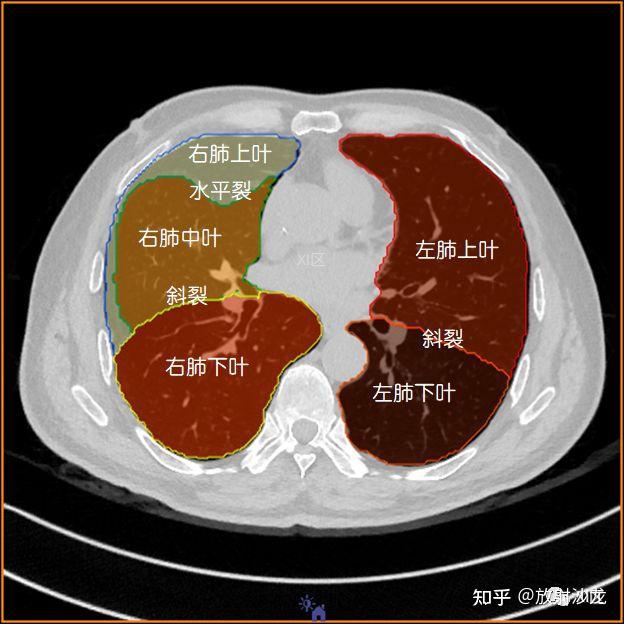

肺的ct应用解剖

肺的解剖 ◆左肺 上叶 下叶 ◆右肺 上叶 中叶 下叶